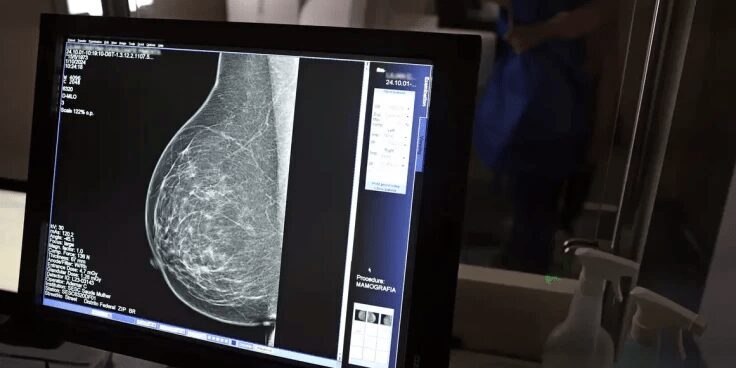

Relatório mostra disparidades regionais e baixa cobertura no Brasil. BRASIL – No mês de conscientização sobre o câncer de mama, um relatório destaca que o acesso aos mamógrafos ainda é um des…